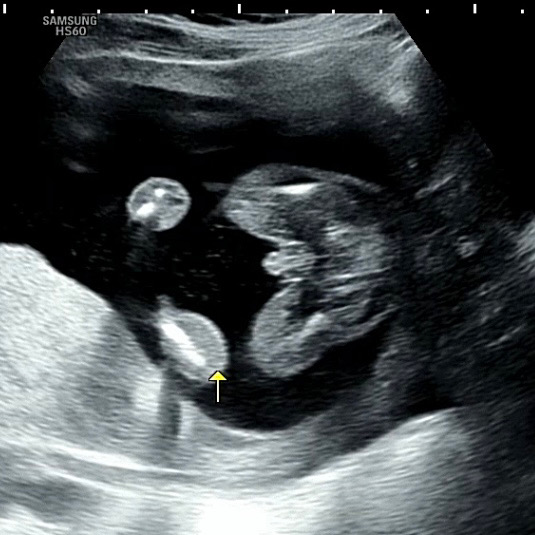

임신 17주 4일 초음파.. 너무(?) 아들이네요!!

내년 7월 1일이 출산예정일인 임산부에요 ㅎㅎ 이리보고 저리봐도 너무 든든한 아들이네용^_^ 가입하고 처음써보는 글인데 다들 힘내셔용!!

어머 이렇게 확실할수가요!ㅎㅎ 초음파도 선명하고 오동통 다리 엉덩이 넘 귀여워요❤️